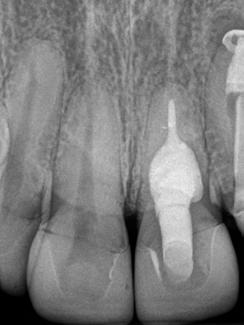

Paciente del género femenino, 44 años de edad, asistió al consultorio para realizar el retratamiento endodóntico del diente 22. Hemos hecho la radiografía inicial para evaluar el diente 22 y nos encontramos con una imagen radiolúcida en forma de globo, caracterizando una reabsorción radicular interna en el diente 21. Hemos hecho, entonces, una nueva radiografía para evaluar el diente 21 (Figura 1).

Figura 1 - Radiografia inicial

Después del análisis clínico, radiográfico y tomográfico, se estableció el diagnóstico de reabsorción radicular interna, sin comunicación externa, lo que hace el pronóstico más favorable.

En la segunda sesión, 15 días después, realizamos la obturación convencional del tercio apical del canal con gutapercha, llenado de la cavidad reabsortiva con BIO-C ® REPAIR (Angelus, Londrina - Brasil) (Figura 7, 8 y 9), condensándolo contra las paredes con condensadores específicos y bolita de algodón humedecida y realizamos el sellado coronario con resina.

8 - Radiografia final